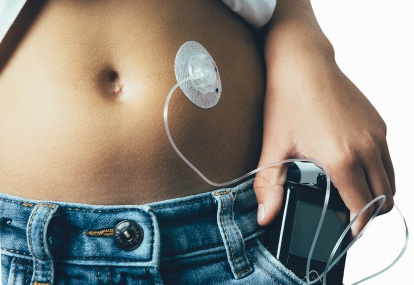

A 23-year-old man presented to his general practitioner with complaints of osmotic symptoms for the past six weeks

His Body mass index (BMI) is 23.6kg/m2. He confirms a family history of diabetes on his father’s side and admits to being busy with his daily physical activities. He has a...